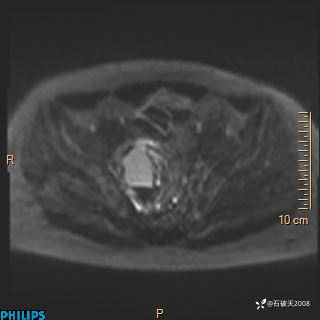

现病史:7个月前患者因骶尾部占位就诊于北京大学人民医院,MRI示:骶骨右侧及右骶前占位,考虑骨巨细胞瘤可能,动脉瘤样骨囊肿可能,神经源性肿瘤待排。行手术治疗,术后病理回示:XXXXX。术后给予对症治疗,具体不详,恢复良好。近几个月反复出现发热,伴骶尾部不适,多次住院给予对症治疗,2天前患者无明显诱因再次发热伴骶尾部不适,无大小便失禁,为求进一步治疗,遂门诊来我院,在门诊初步检查后,以“骶尾部肿物”为诊断收入我科。入院来患者神志清,精神一般,饮食睡眠可,大小便无明显异常,体重无下降。

2023年3月份MRI影像

增强轴位